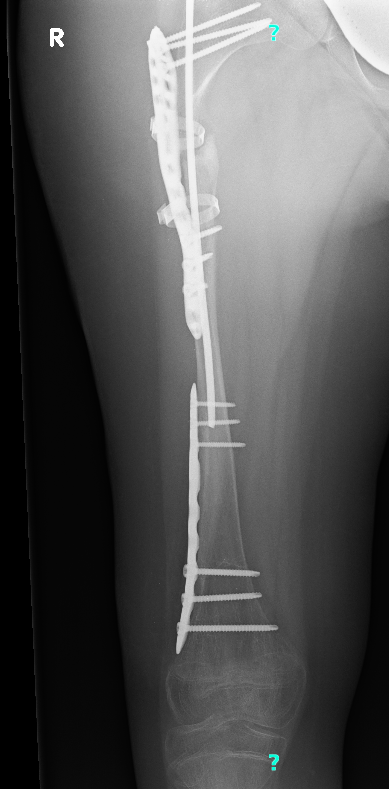

Még mindig lábadozik a júniusi műtétje után, ami sajnos nem a tervek szerint alakult. Egy egyszerű fémcserére készültünk, de végül öt és fél órás, nagy beavatkozás lett belőle. A műtőasztalon, minden óvatosság ellenére, két helyen tört el a combcsontja az orvos kezében. Most lemezek és csavarok tartják össze a lábait. A másik combja is rossz állapotban van, így újabb műtét vár rá.